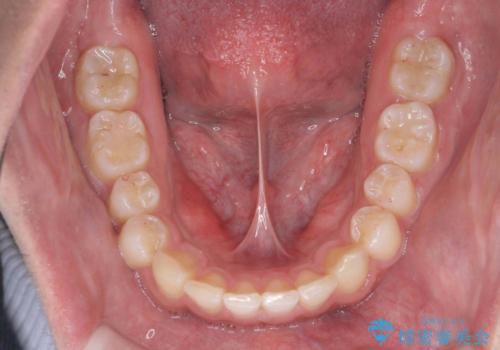

出っ歯が気になる 歯をぬかずに治療

- 前歯が出ているのを気にして来院。

左のかみ合わせが1本分ずれていましたが、機能的には問題ないのでそのまま変えずに治療しています。

ずれている分を、上の歯を1本抜くか(ワイヤー矯正になります)、右上の奥歯を1本分後ろに送るか、そのまま前歯を並べるのかを選んでいただきました。

右のかみ合わせをそのままに、最小限の動かし方で見た目を改善しました。